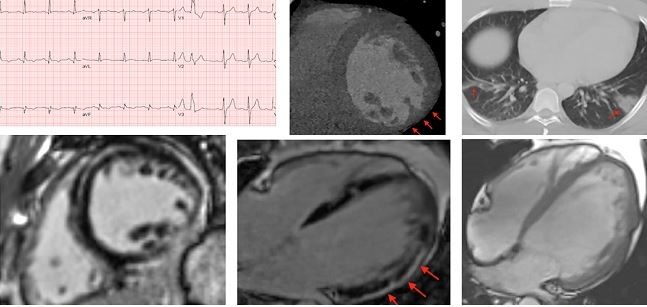

A German autopsy study suggests that at least some of the myocardial injury seen in COVID-19 patients may be related to active virus replicating in heart tissues—an issue of long-running debate with this disease. Though autopsy reports from COVID-19 have been limited, Gregg C. Fonarow, MD, told TCTMD’s L.A. McKeown, “they do give important insights for which there are clinical correlates.”

A German autopsy study suggests that at least some of the myocardial injury seen in COVID-19 patients may be related to active virus replicating in heart tissues—an issue of long-running debate with this disease. Though autopsy reports from COVID-19 have been limited, Gregg C. Fonarow, MD, told TCTMD’s L.A. McKeown, “they do give important insights for which there are clinical correlates.”

Signs of cardiac damage are seen on CMR even in younger, nonhospitalized COVID-19 patients, according to a study in JAMA Cardiology. Despite the fact that 67% of the patients who volunteered for the study never required hospitalization, 78% had abnormal imaging findings 2 to 3 months after testing positive for the virus, TCTMD Managing Editor Shelley Wood reports. Commentators on Twitter raised some issues with the study.

A recent case report in Circulation suggests nonobstructive chest pain symptoms, presumed to be myocarditis in the setting of COVID-19, may actually be extensive and elusive microthrombi, TCTMD’s Caitlin Cox reports. “This type of injury would not be detectable clinically, as no laboratory test specifically can detect microthrombi,” the researchers say.

A recent case report in Circulation suggests nonobstructive chest pain symptoms, presumed to be myocarditis in the setting of COVID-19, may actually be extensive and elusive microthrombi, TCTMD’s Caitlin Cox reports. “This type of injury would not be detectable clinically, as no laboratory test specifically can detect microthrombi,” the researchers say.

Experts provide guidance around the use of multimodality imaging in the evaluation of cardiovascular complications in patients with COVID-19 in the Journal of the American College of Cardiology. “Routine history, physical examination, laboratory testing, electrocardiography, and plain X-ray imaging may often suffice for such patients but given overlap between COVID-19 and typical cardiovascular diagnoses such as heart failure and acute myocardial infarction, need frequently arises for advanced imaging techniques to assist in differential diagnosis and management,” they say.

The wide-ranging cardiac effects during the acute phase of COVID-19 are now well established, but the potential long-term impact of the disease on the heart remains unclear. TCTMD Managing Editor Shelley Wood spoke with researchers looking into that question. “With this disease,” said John P. Greenwood, MBChB, PhD, “we’ve got no idea of what the sort of short- to medium-term outcomes are going to be and certainly no idea what the long-term outcomes are going to be from a heart perspective.”

The wide-ranging cardiac effects during the acute phase of COVID-19 are now well established, but the potential long-term impact of the disease on the heart remains unclear. TCTMD Managing Editor Shelley Wood spoke with researchers looking into that question. “With this disease,” said John P. Greenwood, MBChB, PhD, “we’ve got no idea of what the sort of short- to medium-term outcomes are going to be and certainly no idea what the long-term outcomes are going to be from a heart perspective.”